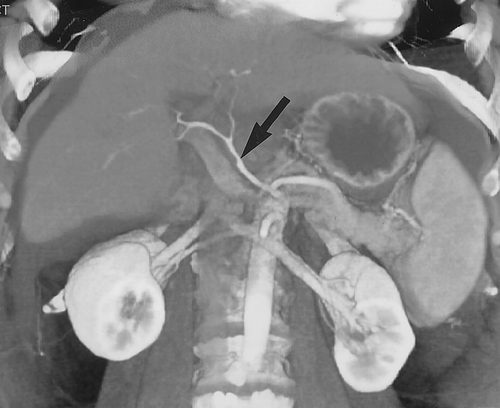

Evaluation of Cirrhosis.— The ability to evaluate the liver in multiple phases of enhancement is ideal for the evaluation of hepatic parenchymal disease. The portal venous phase is best for defining the patency of the portal vein and the SMV and the patterns of collateral flow. Whether the collateral vessels are dilated coronary veins, gastroepiploic veins, or splenorenal veins, three-dimensional CT angiographic mapping is ideal for defining the extent and location of these vessels (Figs 13,14 ). This information may be helpful in biopsy planning and in evaluating potential transplant candidates.